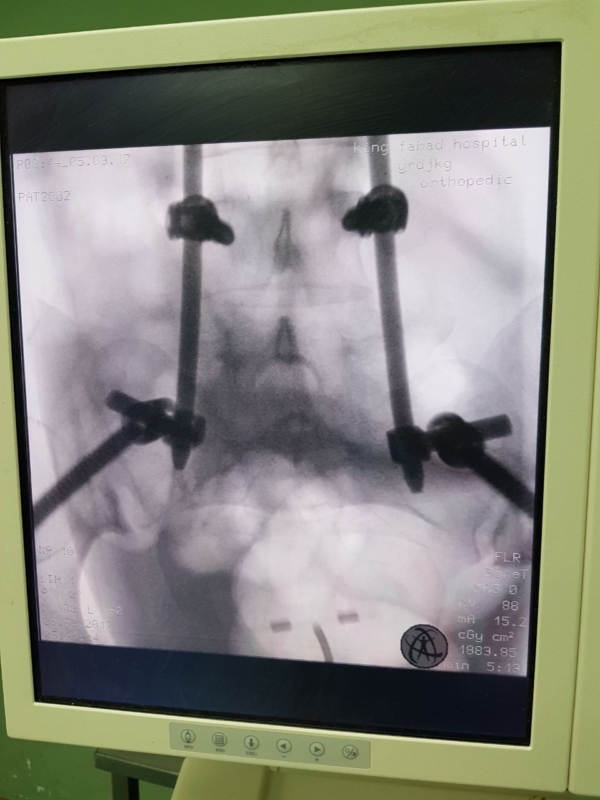

مستشفى الملك فهد في المدينة يثبّت العمود الفقري لأربعينية

أعلنت مديرية الشؤون الصحية في منطقة المدينة المنوّرة، نجاح عملية تثبيت للعمود الفقري بالحوض، دون فتح، بنظام “MISS”، في مستشفى الملك فهد، التي تعتبر الأولى من نوعها.

وأوضحت أنَّ “المريضة (42 عامًا) أصيبت بحادث مروري نتج عنه إصابة بليغة في الحوض (في الجهتين اليمنى واليسرى)، وبعد إجراء الفحوصات الطبية اللازمة لها، تم إدخالها لغرفة العمليات وتثبيت الفقرة القطنية الخامسة بالحوض، بمسامير وقضبان، دون فتح”.

وأبرزت أنّه “تكللت ولله الحمد هذه العملية بالنجاح، في حين يتوقع بإذن الله خروج المريضة من المستشفى في الأيام المقبلة، بعد تماثلها للشفاء”.

يذكر أنَّ مستشفى الملك فهد بالمدينة المنورة بدأ العمل بنظام تثبيت كسور العمود الفقري بدون فتح بنظام “MISS” للحالات التي تناسب هذا النوع من التثبيت.